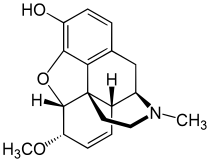

In the 19th century, two major scientific advances were made that had far-reaching effects. Around 1804, German pharmacist Friedrich Sertürner isolated morphine from opium. He described its crystallization, structure, and pharmacological properties in a well-received paper in 1817.[211][213][208][214] Morphine was the first alkaloid to be isolated from any medicinal plant, the beginning of modern scientific drug discovery.[211][215]

Several semi-synthetic opioids were developed in Germany in the 1910s. The first, oxymorphone, was synthesized from thebaine, an opioid alkaloid in opium poppies, in 1914.[228] Next, Martin Freund and Edmund Speyer developed oxycodone, also from thebaine, at the University of Frankfurt in 1916.[229] In 1920, hydrocodone was prepared by Carl Mannich and Helene Löwenheim, deriving it from codeine. In 1924, hydromorphone was synthesized by adding hydrogen to morphine. Etorphine was synthesized in 1960, from the oripavine in opium poppy straw. Buprenorphine was discovered in 1972.[228]